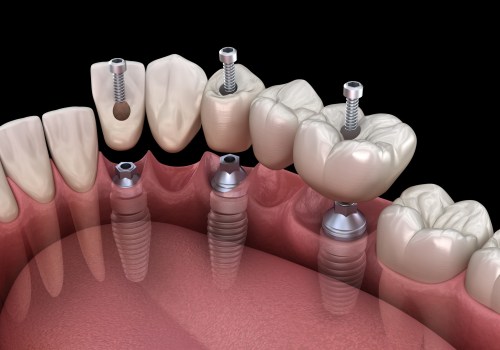

What are Dental Implants and How Can They Help You?

Dental implants are medical devices that are surgically implanted in the jaw to restore a person's ability to chew or...